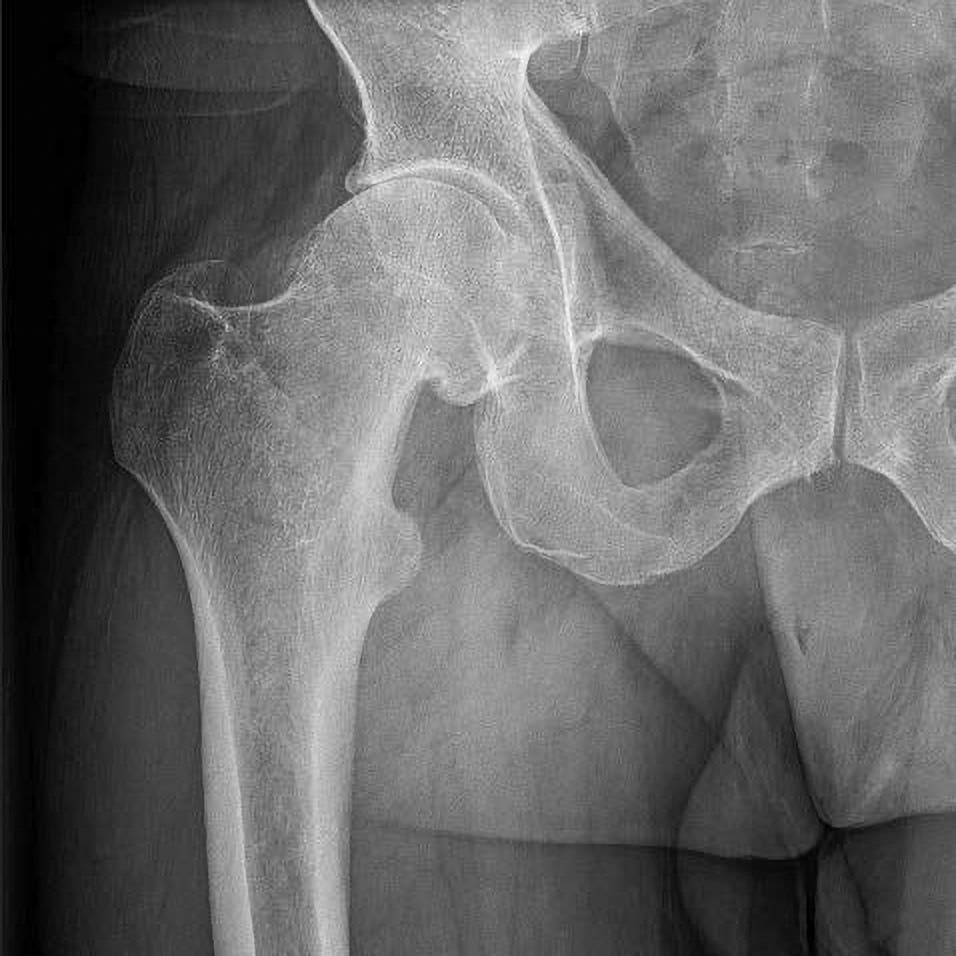

Die Röntgenaufnahme lässt erkennen, dass der Gelenkspalt deutlich verengt ist.

Manchmal geben mir Patienten ihre Röntgenbilder und fragen mich dann, ob sie operiert werden müssen. Unseren jungen Kolleginnen und Kollegen vermitteln wir schon zu Beginn ihrer Facharztausbildung einen wichtigen Satz: »Man operiert kein Röntgenbild.« Zuerst kommen das ausführliche Patientengespräch und die genaue ärztliche Untersuchung; auf das Röntgenbild kann man am Ende schauen. Das Gespräch liefert wichtige Hinweise: Wie äußert sich der Schmerz, welche Schmerzmittel werden genommen, gibt es Probleme beim Laufen? Ein klassisches Zeichen für Arthrose ist eine eingeschränkte Beweglichkeit der Gelenke. Eine fühlbare Schwellung der Gelenkkapsel gehört ebenfalls dazu, sie kann auf einen Gelenkerguss infolge übermäßiger Reizung hindeuten. Bei höhergradigen Arthrose-Stadien sind die Gelenke oft bereits steifer und die Bänder weniger elastisch. Das deutet auf Umbauvorgänge in Richtung Verknöcherung hin. Als Letztes kommt die Bildgebung, und da wünschen sich viele Patienten eine Kernspinuntersuchung. Die braucht es im ersten Schritt aber gar nicht. Mit einem klassischen Röntgenbild in Verbindung mit dem Patientengespräch und der ärztlichen Untersuchung können erfahrene Orthopädinnen und Orthopäden eine zuverlässige Ersteinschätzung vornehmen.

Bei einer Hüftgelenksarthrose verschleißt der Knorpel des Gelenkkopfes und der Gelenkpfanne. Der Prozess schreitet in Stadien voran, was hier an Modellen gezeigt ist (von rechts nach links fortschreitend; bläulich: Knorpel). Dabei bilden sich Knochenvorsprünge und Entzündungen im und um das Gelenk. Bei einer Gelenkersatz-OP wird der zerstörte Gelenkkopf mitsamt einem Teils des Schenkelhalses entfernt, der beschädigte Knorpel im Beckenbereich ausgefräst und dort eine künstliche Hüftpfanne eingesetzt (ganz links). In den Oberschenkelknochen setzen die Chirurgen einen künstlichen Hüftschaft mit Kopf (rosa). Dieser gleitet anschließend in der eingepflanzten Hüftpfanne.